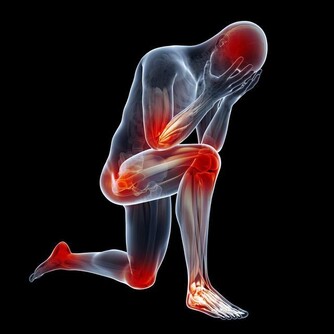

這六種走路姿勢,正在悄悄損傷肌肉和關節!

是的,走路人人都會,但不一定都對,你以為沒問題的走姿,可能正是你腰酸背痛的“罪魁禍首”。